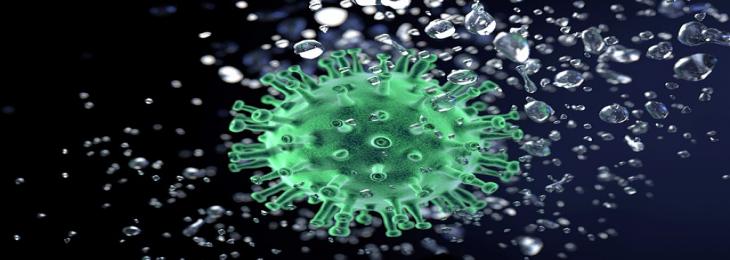

A study conducted by a team of researchers from the University of Melbourne studied whether the emergence of more deadly variants of concern (VOCs) of severe acute respiratory syndr...

Scientists from the U.S., Switzerland, and Australia have developed a new COVID-19 vaccine which is more effective against new variants of severe acute respiratory syndrome coronavi...

A team of researchers from South Africa after continual genomic surveillance of the SARS-CoV-2 strains identified new sequences in South Africa, which are distinct from C.1....

A team of researchers from the Rockefeller University, U.S. conducted a study that stresses on antibody evolution after vaccination against severe acute respiratory syndrome coronav...

A team of researchers from the Kumamoto University and Weizmann Institute of Science revealed that mutations of the SARS-CoV-2 spike protein or S protein have the potential to escap...